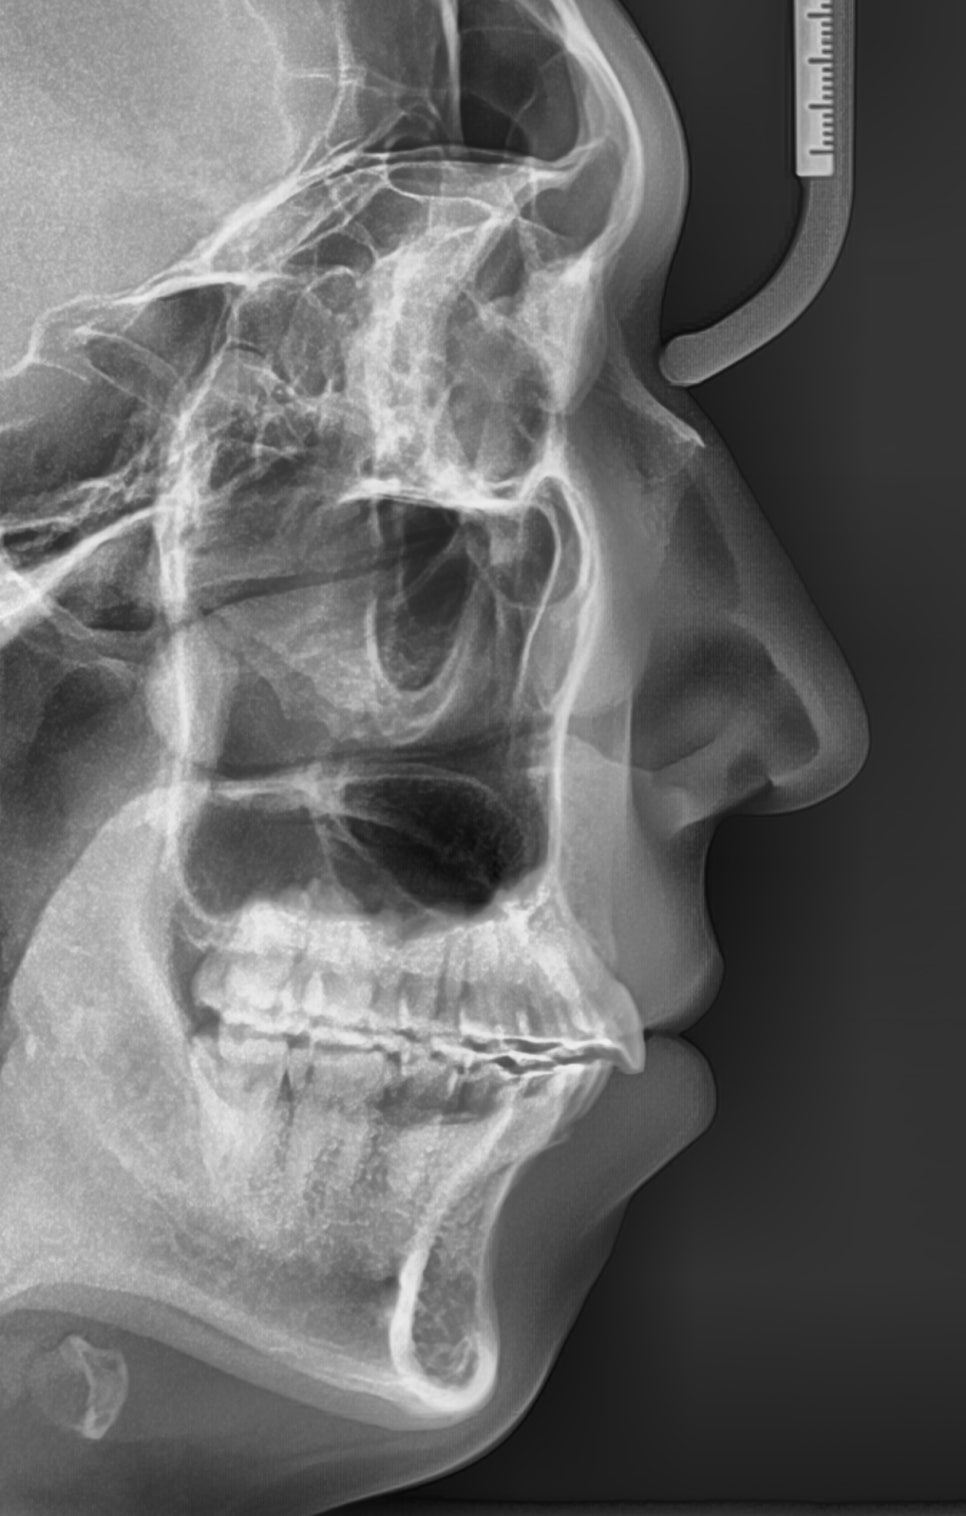

드디어 교정 끝.

2019.8.30.에 저희 병원에 처음 오셨고 1달뒤 치료 시작

2022.9.27.에 치료 끝나셨으니 약 3년간 치료했습니다.

3년 중 약 2년반은 당기기만 했고, 오셔서 고무줄만 갈아끼고 가셨습니다.

약 5mm정도 후방이동 된 것으로 보입니다.